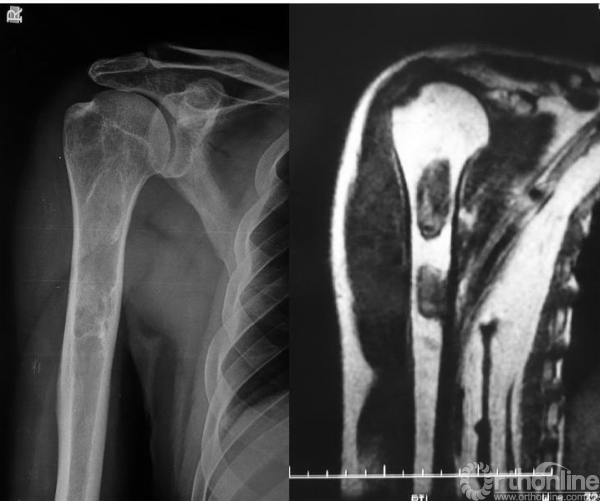

本病女性多见,男女发病率约为1.2:3,多在10岁左右发病,主要症状为轻微疼痛,局部肿胀及压痛。因症状轻微往往被忽略,多数病例是在以后查体或发生病理骨折时才被发现,骨折时疼痛可突然加重,肢体功能障碍,但骨折很少移位(图1),由于受累骨的坚固性受到明显影响,肢体可出现弯曲畸形,发生于股骨近端的常形成髋内翻,被称为“牧羊拐畸形”(图2)。

图1 股骨病理性骨折,没有明显的移位

图2 牧羊拐畸形